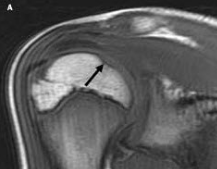

Osteochondral Fracture

<div id="article-content-body"> <p><img alt="" src="/sites/default/files/images/Con1PESporOFa.jpg" style="border:1px solid black; height:118px;...